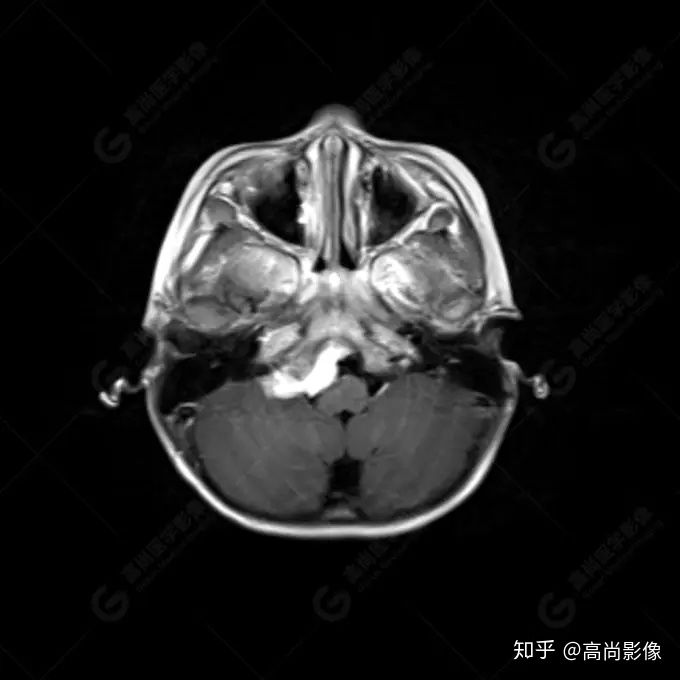

右側(cè)顳葉腫瘤切除術(shù)后(具體不詳):右側(cè)顳部骨質(zhì)不連續(xù)呈術(shù)后改變,右側(cè)顳葉術(shù)區(qū)見片狀長T1長T2信號(hào)影,F(xiàn)LAIR呈低信號(hào);術(shù)區(qū)后方右側(cè)顳枕葉見一巨大占位性病變影,邊界欠清,大小約6.2×5.8×4.3cm(前后×左右×上下),信號(hào)不均勻,T1WI呈等稍低信號(hào)間雜少許高信號(hào),T2WI呈高稍低混雜信號(hào),DWI示部分病灶彌散受限,相應(yīng)ADC圖減低,磁敏感序列見部分呈極低信號(hào),增強(qiáng)掃描可見明顯不均勻強(qiáng)化,鄰近硬腦膜及小腦幕增厚并明顯強(qiáng)化;另延髓右前方及右側(cè)橋小腦角區(qū)見一不規(guī)則形異常信號(hào)影,大小約3.2×1.3×3.7cm(左右×前后×上下),呈長T1稍長T2信號(hào),F(xiàn)LAIR呈等信號(hào),DWI未見受限,增強(qiáng)后明顯均勻強(qiáng)化,鄰近腦膜明顯強(qiáng)化。鄰近腦實(shí)質(zhì)及右側(cè)顳角明顯受壓;左側(cè)大腦半球未見局灶性信號(hào)異常,中線結(jié)構(gòu)稍左移。